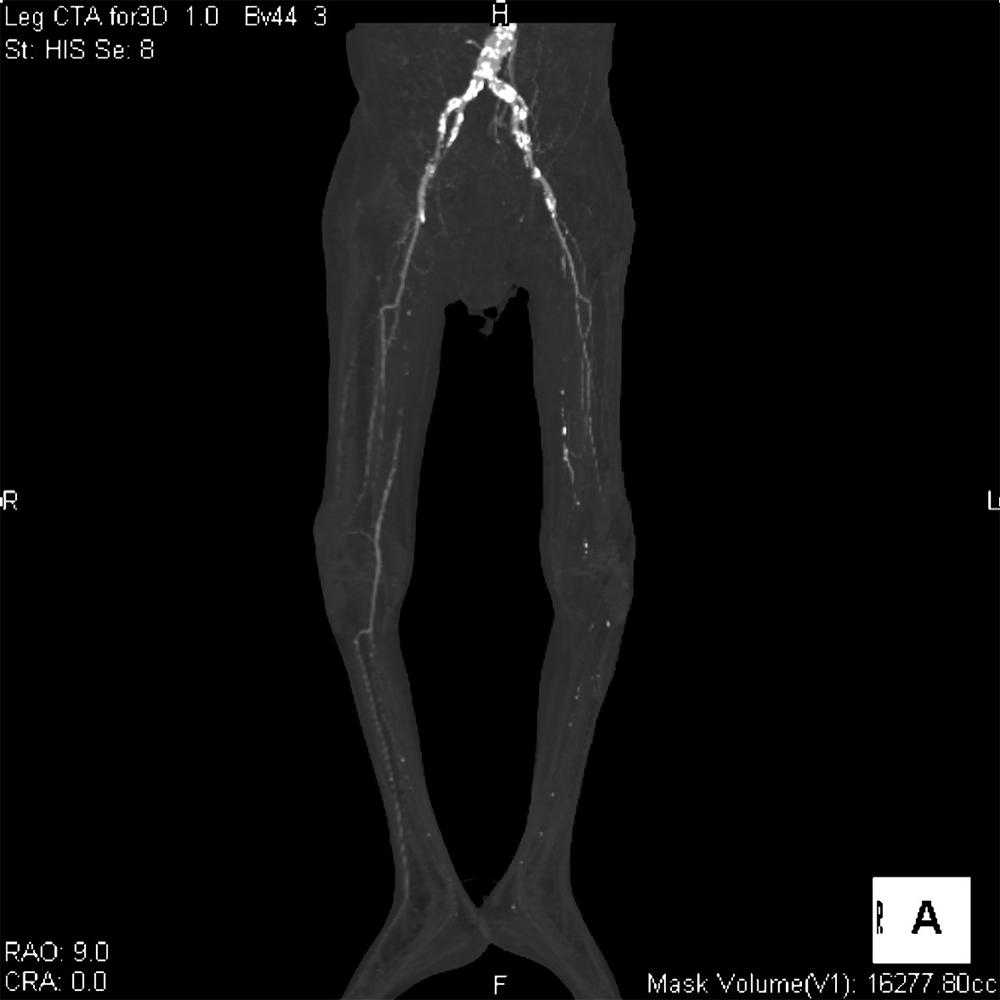

60代男性。高血圧、糖尿病、脂質異常症、喫煙など多数の既往がある。他院にて進行する下肢壊疽を認め、切断目的に当院に転院。入院1日目に下肢造影ダイナミックCTが施行された。動脈相で両側浅大腿動脈近位に閉塞を認めた。右下肢では側副路を介して膝窩~下腿三枝の細い描出が確認されたが、左下腿三枝の描出は認められなかった。左下腿の軟部組織は腫脹し、対側にくらべ造影効果の減弱と多量のガス像も見られたことから左優位の閉塞性動脈硬化症に伴う左下腿壊疽と診断した。感染コントロール困難で入院2日目に急変し死亡した。

当該疾患の診断における造影CTの役割

下肢造影CTを撮像すると下肢動脈の狭窄形態や病変前後の血管走行、石灰化やプラークなど血管壁の性状評価、側副血行路の評価、多発病変の有無、その他に潰瘍病変、動脈瘤、解離の有無など非常に多くの情報を得ることができる。症例によっては遅延相を追加することで静脈の走行や位置関係の他、静脈内血栓の評価も行うことができる。さらに多断面再構成像や3次元像を構築することで血管の状態をイメージしやすくなり、その後の治療においてはカテーテルによる血行再建術のリファレンスとして使用するなど治療にも大変有用な検査と考えられる。治療後においては効果判定や合併症の有無、その後の経過観察に有用である。